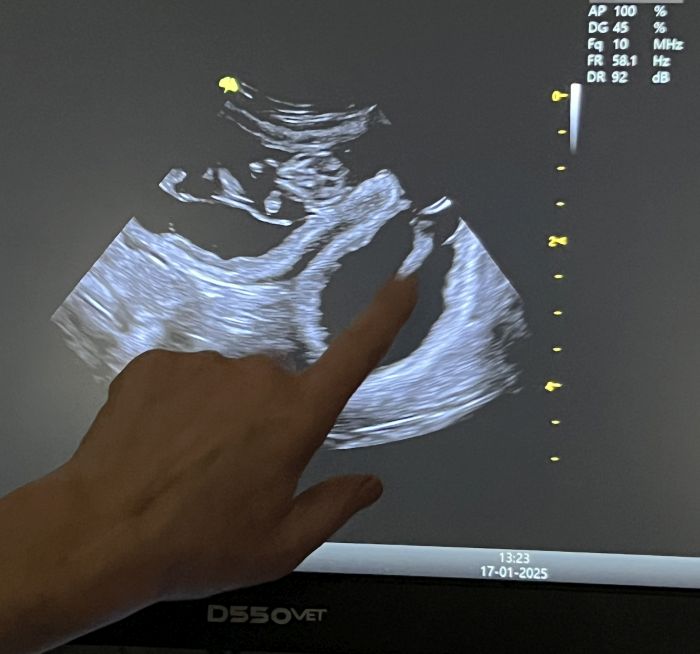

Kurz nach der Ankunft der Samtpfoten war es auch schon so weit: Zwei Katzen brachten ihre niedlichen Jungen zur Welt. Und es ist einfach herrlich anzusehen, wie toll sich die beiden Mamas und ihre Babys kümmern. Doch der Spruch „Ende gut, alles gut“ passt hier leider nicht. Denn anscheinend war auch noch eine dritte Katze trächtig. Das wurde auf einem Ultraschallbild deutlich. Doch das Drama folgte auf dem Fuße. Auf der Facebookseite des Tierheims in NRW heißt es dazu: „Wir hatten schon alles vorbereitet, aber gestern Abend hatte sie eine Fehlgeburt. Wir waren an ihrer Seite, konnten aber nicht viel tun.“

Das Ganze ist bereits am 17. Januar passiert. Doch die Ursache bleibt laut Facebook-Post unklar. Das Tierheim in NRW kann nur spekulieren. Es könnte sowohl an „Inzucht, mangelnder Versorgung im alten Zuhause, Stress beim Einfangen, dem jungen Alter der Katze“ oder weiteren Gründen gelegen haben.